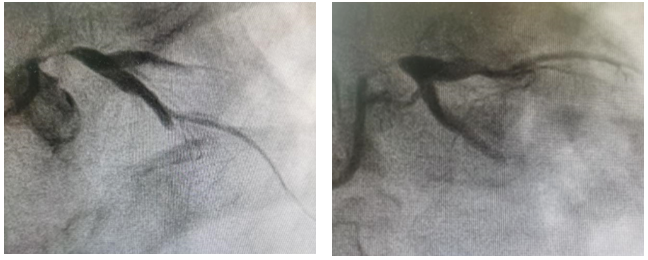

造影结果

LM:开口及体部次全闭塞,血流TIMI0-1级;

LAD:弥漫斑块浸润伴中度钙化,近段弥漫狭窄20-30%,中段局限狭窄80%,血流TIMI0级;

LCX:斑块浸润,血流TIMI0级;

RCA:斑块浸润,血流TIMI3级,向LAD及LCX提供侧枝循环。

▲ 最后造影结果理想满意